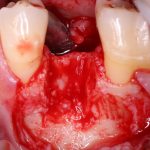

Возвращаемся к основной операционной области. Еще раз посмотрим на альвеолярный гребень, поофигеваем от его ширины и моих грандиозных планов:

Я зафиксировал костный блок практически без адаптации на несколько винтов. Обрати внимание, что винты находятся в зоне, где не планируется установка имплантатов. Фиксация должна быть надежной, поскольку мне еще предстояла подготовка лунок для имплантатов. Трех винтов для этого вполне достаточно.

Дальнейшая адаптация костного блока свелась к сглаживанию острых краев. После чего я приступил к подготовке лунок и установке имплантатов.

Глянем на то, что получилось:

Осталось адаптировать костный блок (убрать острые края), проверить его фиксацию и, при необходимости, добавить винты. Десятисекундное дело.